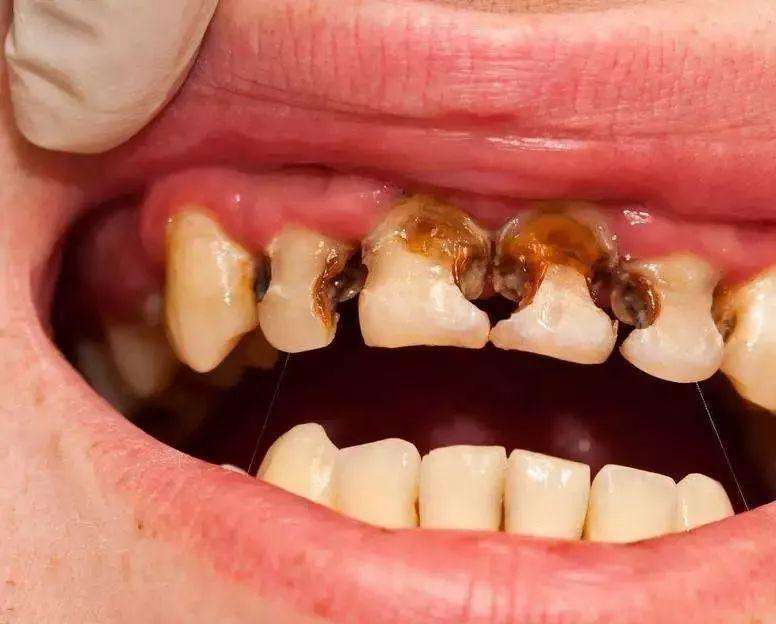

什么是根管治疗呢?所谓根管治疗,又称牙髓治疗,是治疗根尖周病或牙髓病最有效的技术。它通过清除根管内的坏死物质和发炎的牙髓,并进行适当的消毒,填充根管,以去除根管内的容物对根尖周围组织的不良刺激。根管治疗这种治疗方式不仅使牙齿得以保留,还能与拔牙术互补呢!一般牙齿因龋齿有洞,外部细菌侵入到牙髓腔,导致牙髓受到细菌感染而发炎的或是细菌侵入牙槽骨里,引起牙根尖周围组织发炎的,都需要进行根管治疗。

对根管治疗不了解的患者一听到这个名字就感到莫名的害怕。但想想,如果不做根管治疗,牙齿越往后越可能出现疼痛,阵痛,夜间痛,口臭等后果。牙齿如若病变到一定程度,后续也只能将其拔除,此时就算想做根管治疗,也无济于事。

根管治疗也不同于过去所说的”杀神经“。在以前,如果遇上牙髓发生炎症,引发疼痛,一般会采用将牙齿钻开,使用药物将牙齿内部发炎的牙髓统统杀死,从而缓解疼痛。但随着治疗观念的全面革新和现代口腔医学技术的进步,这种老套的方法逐渐被淘汰。相比于”杀神经“,根管治疗的修复效果会更彻底,能进行更加彻底的清理和严格的消毒,并用人工的充填材料将”根管“严密填塞。